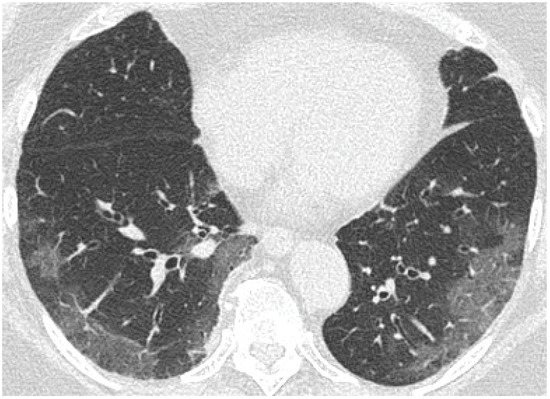

2.2. Chest Computed Tomography

- GGO was defined as hazy increased attenuation of lung with preserved bronchial and vascular margins;

- Consolidation was considered an increase in pulmonary parenchymal attenuation that obscures the airways and vessels;

- Crazy paving was the area of GGO with coexisting thickening of interlobular septae;